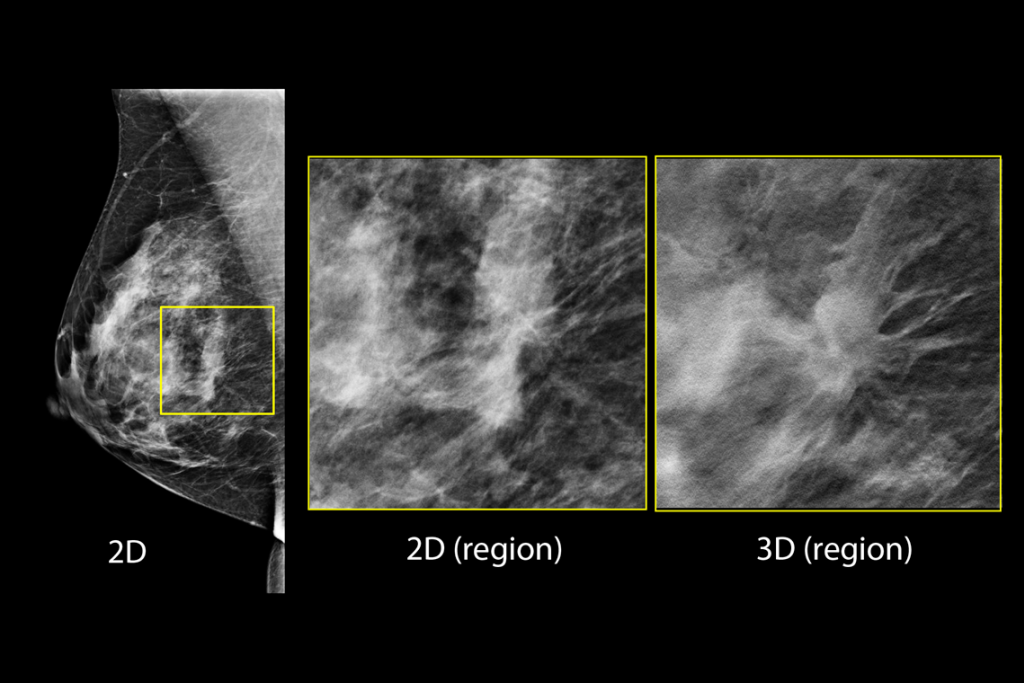

Immagini cliniche di una mammografia

Immagini cliniche di una mammografia con tessuto mammario denso